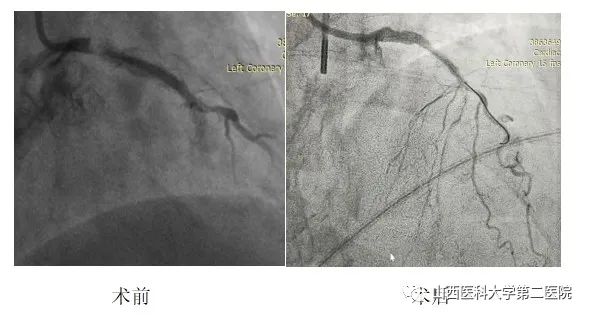

患者刚上手术台时,由于心情紧张,心绞痛发作,杨滨主任团队按照既定方案,立即置入主动脉内球囊反搏(IABP),同时快速完成冠脉造影。造影显示,冠脉三支左主干病变,伴严重钙化,病变高危复杂,手术风险极高。团队再次向患者家属告知病情,家属表示理解,愿意承担手术风险。随后,整个团队开始紧张有序地实施介入手术,置入指引导管、导丝小心通过病变部位、磨头高速旋磨主干钙化病变、球囊预扩张、最后植入支架。手术历时两个小时顺利完成,大家终于松了一口气。